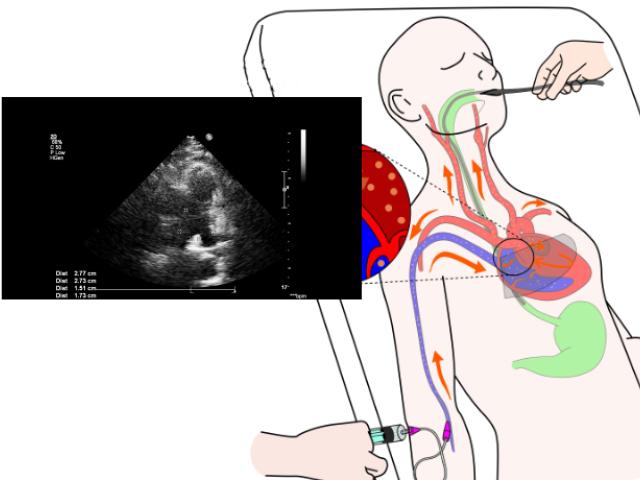

Un ecocardiograma transesofágico (ETE) es un procedimiento que utiliza el ultrasonido para producir imágenes en movimiento en tiempo real del interior del corazón.